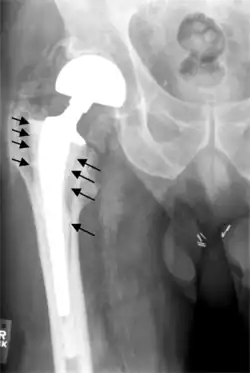

Fracture

Intraoperative fractures may occur. After surgery, bones with internal fixation devices in situ are at risk of periprosthetic fractures at the end of the implant, an area of relative mechanical stress. Post-operative femoral fractures are graded by the Vancouver classification.[37][38]